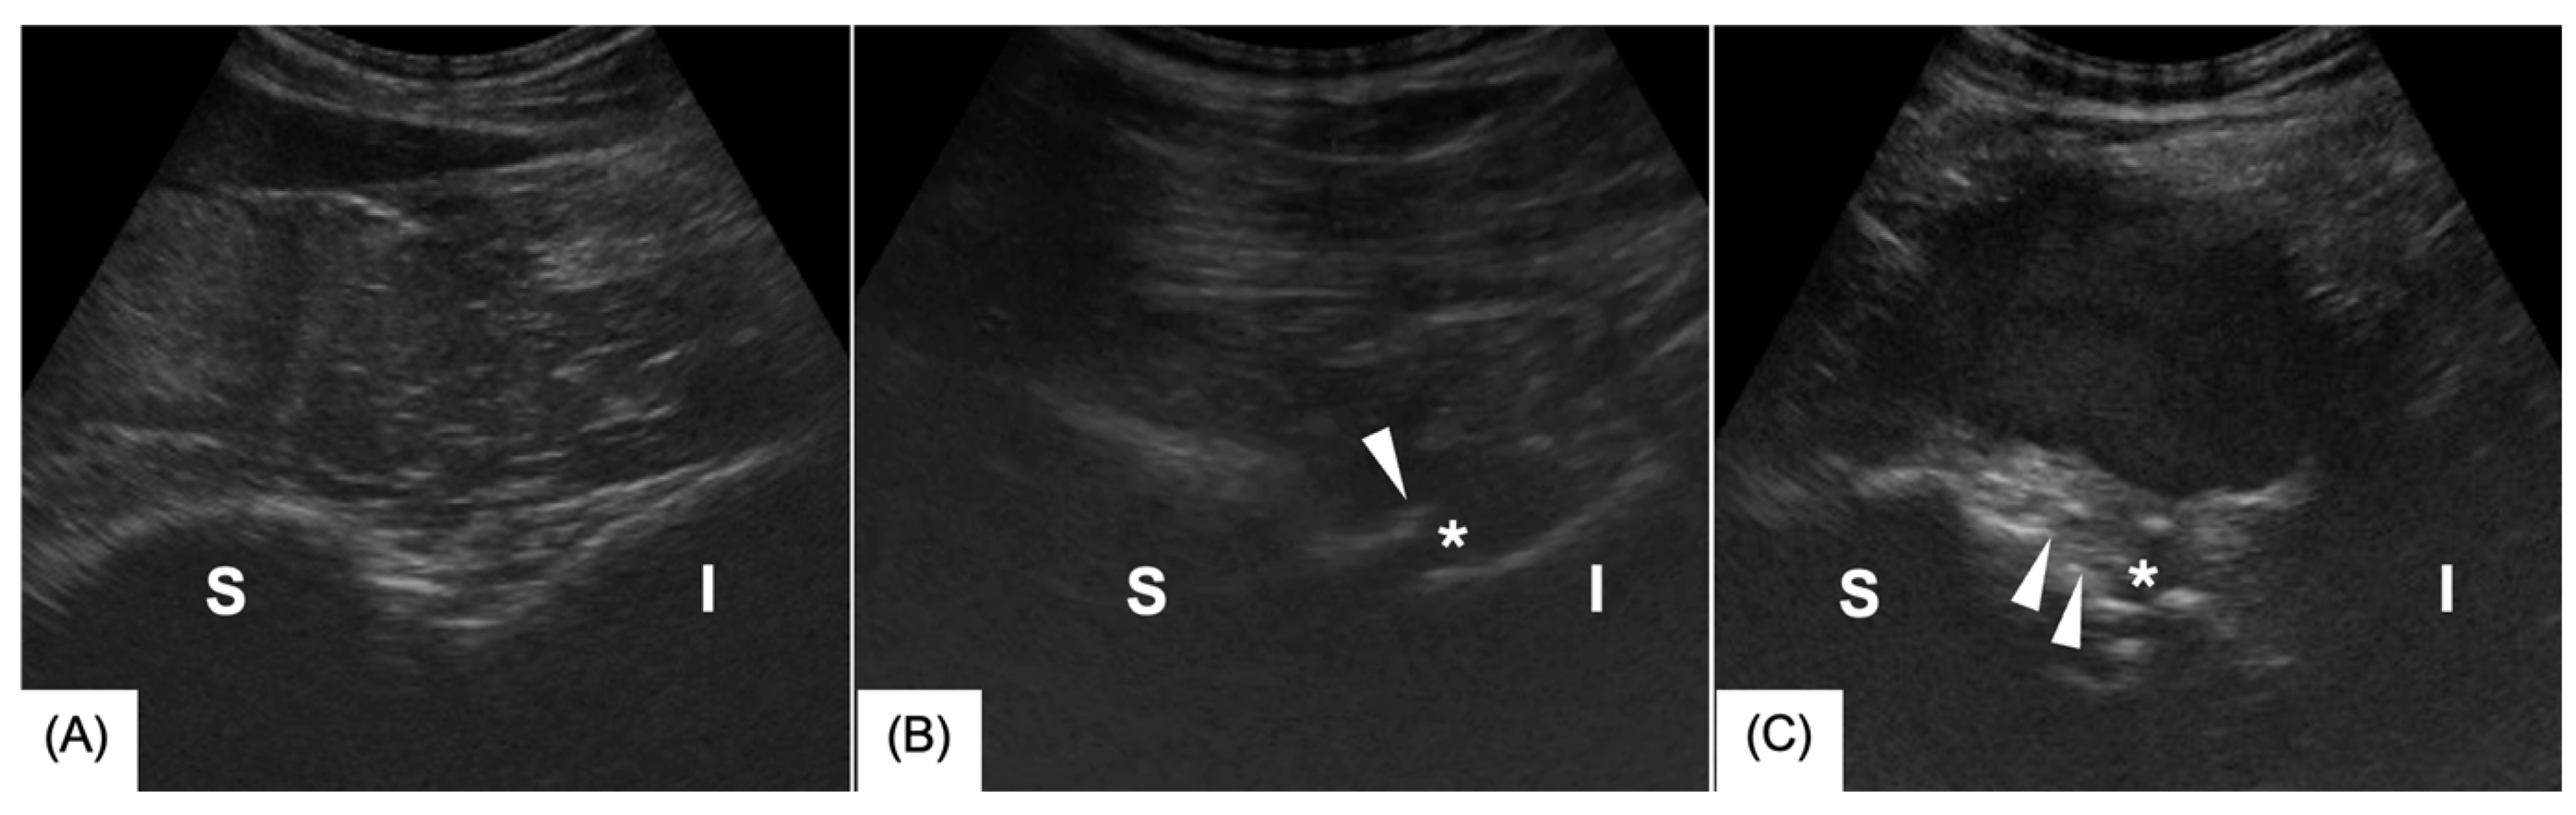

3.1. Ultrasonography